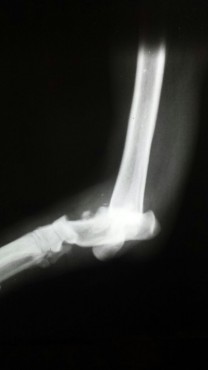

Casos Interessantes > ARTRODESE Tíbio-Tarsica por placa medial

Veja algumas Fotos